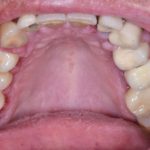

Fig. 9 Pigmentazione simmetrica e diffusa del palato duro di colore bluastro indotta da Imatinib.

Home L’odontoiatria e le reazioni avverse a farmaci delle mucose orali Fig. 9 Pigmentazione simmetrica e diffusa del palato duro di colore bluastro indotta da Imatinib.